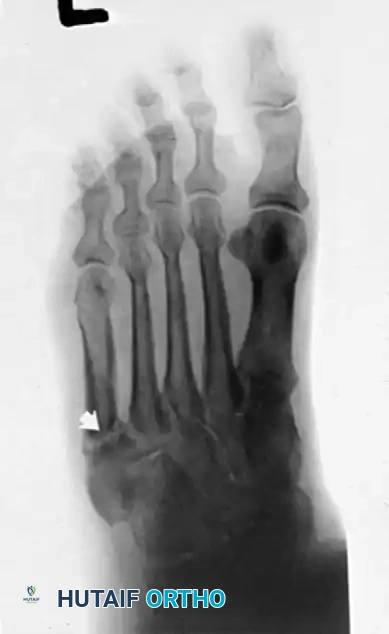

- Plain Radiographs: Weight-bearing anteroposterior, lateral, and mortise views of the ankle and foot are obtained to rule out fractures (e.g., "fleck sign" indicating SPR avulsion), os peroneum pathology, or varus hindfoot alignment.

Radiographic evaluation of the foot and lateral column.